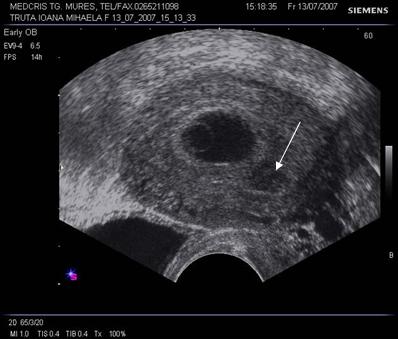

Fig nr 6 Decolare de pol inferior ( cu sageata ) la o sarcina de 7 sapt

Fig. nr. 66. Aceeasi sarcina, ca in figura precedenta, la 12 saptamani , fara imagini patologice la polul inferior ovular, marcat cu sageata

Fig nr. 67 Decolare de pol inferior ovular, situat in continuarea canalului cervical

( sageata) la ecografia transvaginala